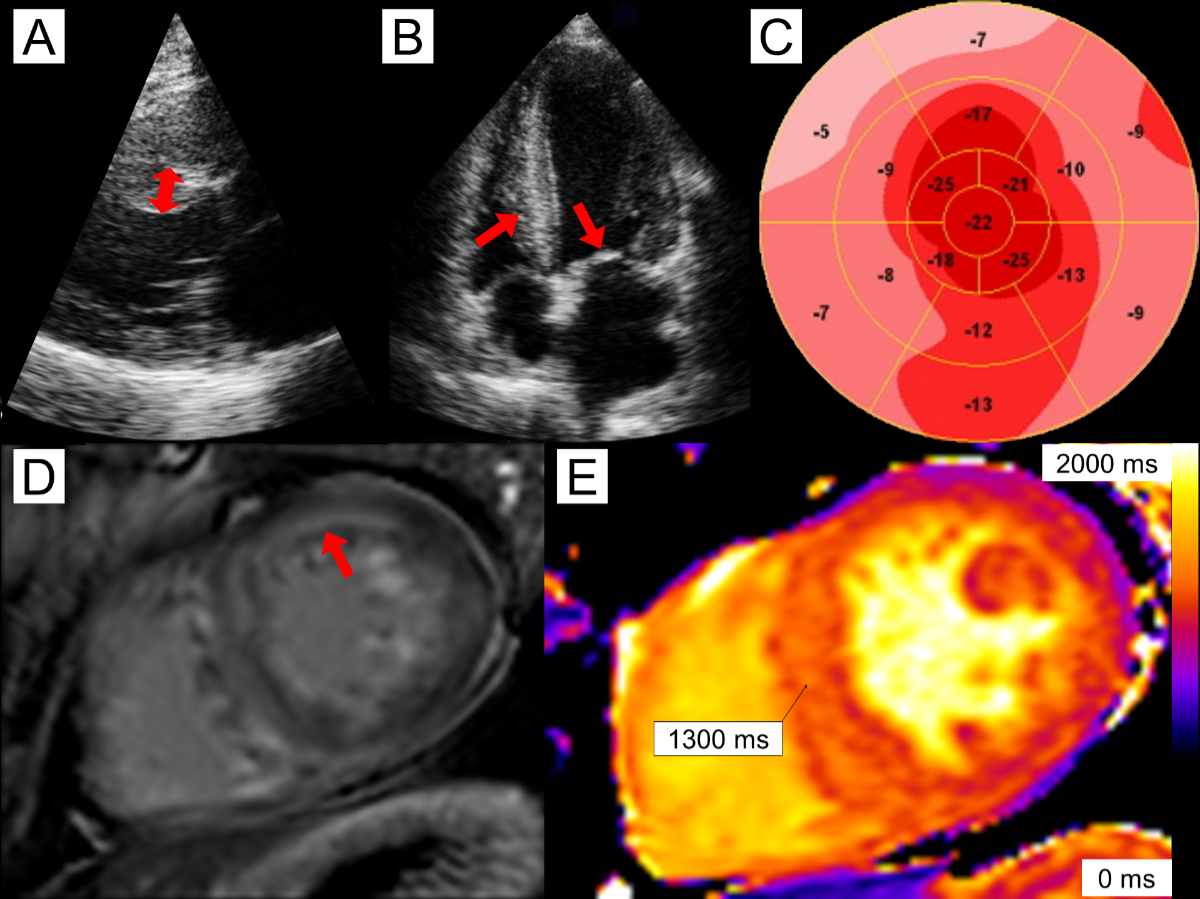

The presence of typical signs and symptoms of cardiac amyloidosis should prompt further testing by echocardiography. Inherently, left ventricular wall thickness represents the diagnostic hallmark of cardiac amyloidosis [20]. The minimal threshold to screen for cardiac amyloidosis has recently been lowered to 12 mm by a European consensus statement [20]. Characteristic echocardiographic findings of cardiac amyloidosis include pleural or pericardial effusion; thickening of the right ventricle, valves or interatrial septum; a low stroke volume; diastolic dysfunction; and a paradoxical low-flow low-gradient aortic stenosis (figure 1) [21]. A reduced longitudinal global strain with apical sparing is another characteristic feature, which may be sensitive but has limited specificity [22]. If echocardiography has a poor acoustic window or echocardiographic findings are not suggestive of cardiac amyloidosis, cardiac magnetic resonance imaging (CMR) may distinguish structural or functional abnormalities better. Typical findings include increased left and right ventricular mass (or at least wall thickness), abnormal gadolinium kinetics, diffuse transmural or subendocardial late gadolinium enhancement, increased T1 mapping or increased extracellular volume, which has the highest specificity above 40% (figure 1) [23, 24]. Even though CMR may be highly suggestive, it is not diagnostic of cardiac amyloidosis.

Figure 1A 56-year-old male with cardiac AL (light chain) amyloidosis. Echocardiography reveals mild asymmetric left ventricular (LV) hypertrophy with septal wall thickness of 14 mm (panel A, double-headed arrow) as well as thickening of the right ventricle (RV) and mitral valve (panel B, arrows). There is reduced global longitudinal strain of –14.3% and relative apical sparing (panel C). Cardiac magnetic resonance imaging reveals diffuse, predominantly subendocardial late gadolinium enhancement (panel D, arrow). Native T1 times were elevated in the septum, measuring 1300 ms (panel E).